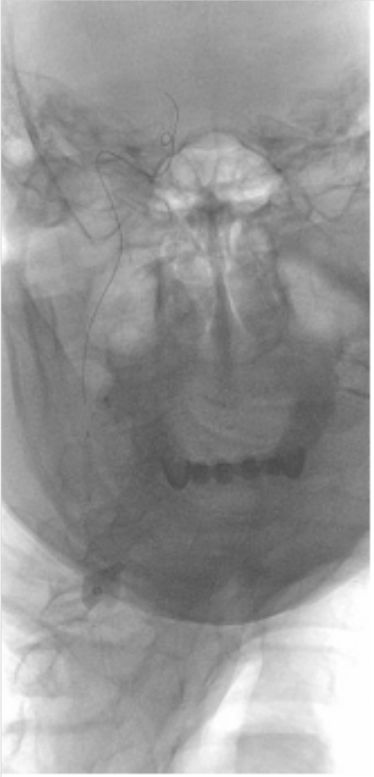

2019-07-05北京军颐中医医院高分辨核磁:

1.右侧颈内动脉夹层形成并血栓形成、管腔闭塞。

2.左侧颈内动脉眼段管腔中度狭窄,局部夹层不排除。

3.右侧大脑中动脉起始部管壁增厚,管腔重度狭窄(图3)。

图3